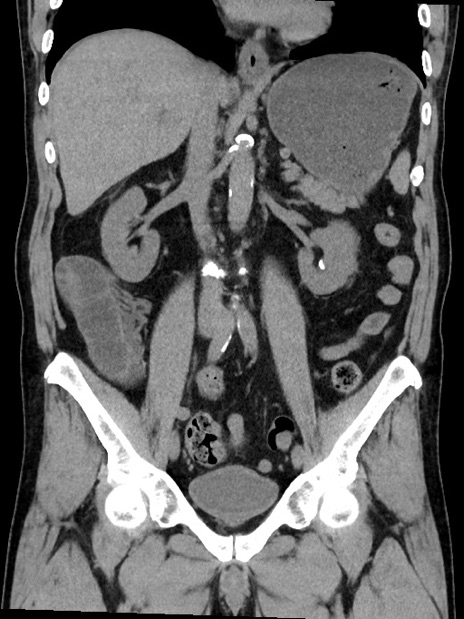

症例35(冠状断像)

【症例】70歳代 男性

【主訴】腹部膨満、嘔吐

【現病歴】昨日より腹部膨満感出現。本日増悪し、仙痛出現。嘔吐あり、受診。

【既往歴】糖尿病、胆摘後

【身体所見】BP 149/80mmHg、HR 74/min、BT 35.9℃、腹部:膨満、軟、圧痛なし。腸雑音減弱あり。上腹部正中切開瘢痕あり。

【データ】WBC 13500、CRP 1.72